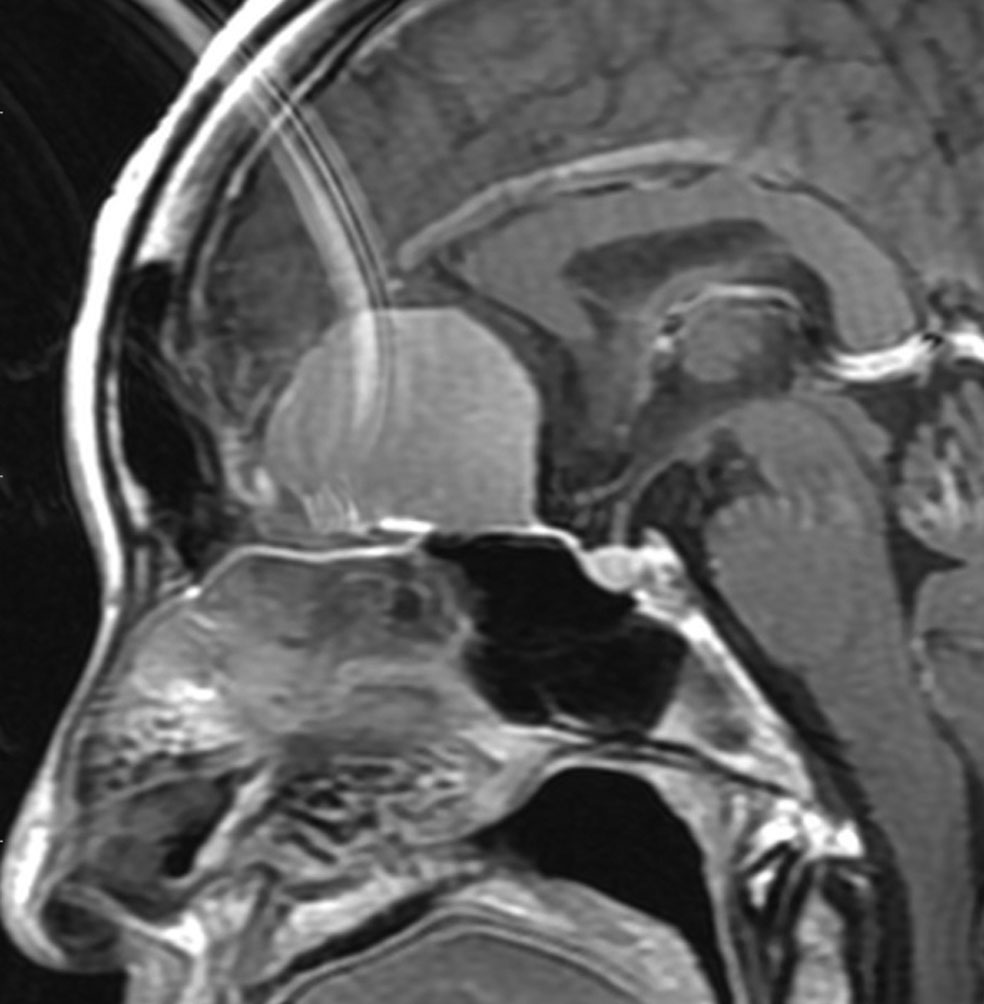

上矢状洞髄膜腫 superior sagittal sinus meningioma

また別な例です。1986年13歳の時に2度の開頭手術を受けましたが,全摘出できずにそのまま経過観察されました。

左の画像は1997年の術前のものです。これを2回に分けて全摘出しました。上矢状洞はやはり冠状縫合のあたりから静脈洞交会まで摘出しました。その下の大脳鎌も全て摘出したので,直静脈洞の上壁を開けることになり,直静脈洞からの激しい出血があり縫合して直静脈洞形成をするのが大変でした。手術後16年が経過しますが再発していませんし,社会人として普通に暮らせています。

この例が教えてくれることは,上矢状静脈洞は全長にわたり切除してしまっても,神経脱落症状を出さないで普通に生きて行かれるということです。